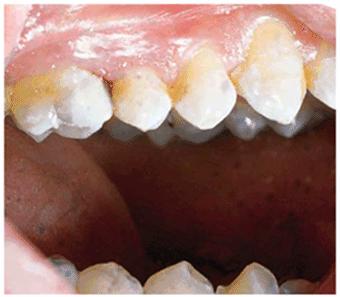

either on an individual tooth or on all teeth (Figures 16-1A, and 16-1B). There are many causes and

Figure 16-1A: An otherwise attractive smile is marred by discolored teeth.

Figure 16-2A and B: Total neglect resulted in severe staining

of this patient's teeth.